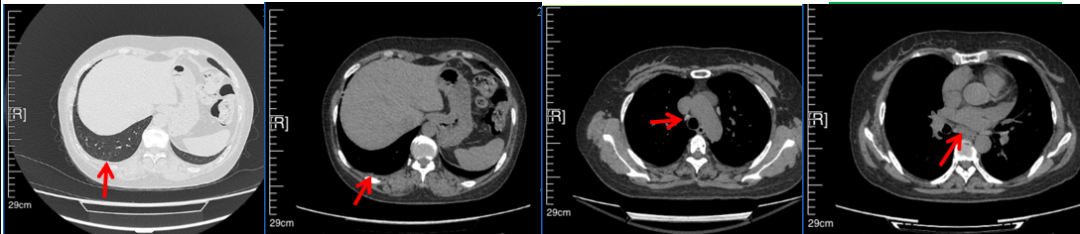

2016年1月复查CT提示支气管截断可见新发小结节,一线治疗采用培美曲塞+DDP方案化疗4周期(培美曲塞3.36,DDP 480mg)。化疗后复查胸部CT:右肺见不规则结节样影,最大层面大小约19mm*8mm,较前比较明显增大,疗效评估PD。2017.3-2017.4予单药多西他赛化疗3周期,疗效评估SD。2018年5月末复查CT提示结节较前增大,评效为PD,2018年6-10月予多西他赛+CBP化疗4周期,疗效评估SD。2022年5月患者出现活动后气短,复查胸部CT示右肺膨胀不良;右侧胸腔积液增多。胸腔积液包埋病理示符合肺腺癌细胞。行NGS基因检测:EML4:exon13-ALK:exon20融合。PD-L1(克隆号22C3)TPS<1%。

临床诊断:右肺上叶恶性肿瘤rT0N0M1a IVA期(第9版分期);恶性胸腔积液。

诊疗经过:2022年5月始口服克唑替尼3个月,出现肝功能异常(DILI 2级伴临床症状),改用恩沙替尼靶向治疗至今,目前评效为维持PR。恩沙替尼应用期间出现轻度肝功能异常(DILI 1级),对症处理后好转。截止目前PFS 33个月。

2018.07

2022.05

2022.08

2023.05

2024.12